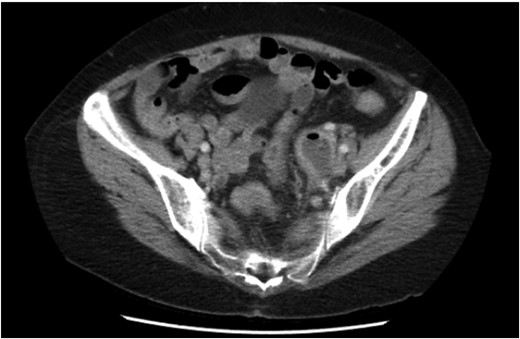

A 65-year-old woman was referred by her general practitioner to the gynaecology service of a metropolitan hospital with a 5-day history of abdominal pain lateralizing to the left iliac fossa, fevers, anorexia and diarrhoea. She was hemodynamically stable and the physical examination revealed marked tenderness to deep palpation and mild guarding in the left iliac fossa. Bimanual examination revealed an exquisitely tender and difficult to define adnexal mass. Her background history included a lower caesarean section, hyperlipidaemia and osteoporosis. No family history of malignancy was present. Interestingly, the initial contrast computed tomography (CT) abdomen and pelvis scan characterized a left tubular adnexal structure with an air fluid level but normal colon, and was reported as pyosalpingitis (Fig. 1). A subsequent pelvic ultrasound scan noted sigmoid thickening. Inflammatory markers were raised with a white cell count of 15.4 × 109 cells/L and CRP of 155 mg/L. Although initially afebrile, she spiked a temperature of 38.4 and commenced IV antibiotics for pelvic inflammatory disease. Given the uncommon presence of gas in the tubo-ovarian abscess and the suggestion of diverticulitis, a general surgical opinion was sought. It was agreed upon that this was most likely acute sigmoid diverticulitis complicated by a local perforation into the left salpingeal tube and ovary.

Initial CT demonstrating a gas containing the left adnexal mass and normal sigmoid colon.